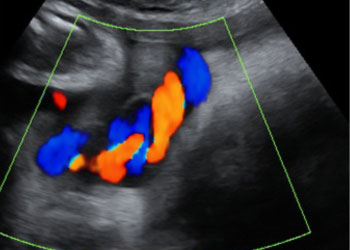

Ejemplos de ecografías del embarazo